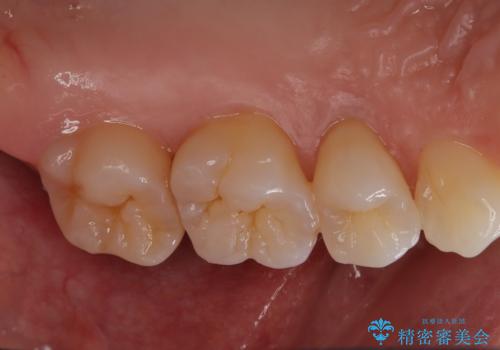

- 定期的にクリーニング(保険適応)に通って頂いている患者さんです。歯周ポケットが4ミリあったため歯茎を開いて歯石を除去するためにオープンフラップ術を行うことにしました。

歯周ポケットがそれほど深くない患者さんでしたが、いざ歯茎を開いてみるとそこにはたくさんの歯石がありました。もし歯周ポケットが4ミリだからと言って放置していれば数年後には、沢山の骨が無くなっていたことが予期出来ます。現段階で歯茎の下にある歯石を除去することにより骨が無くなることを予防する事が出来ました。